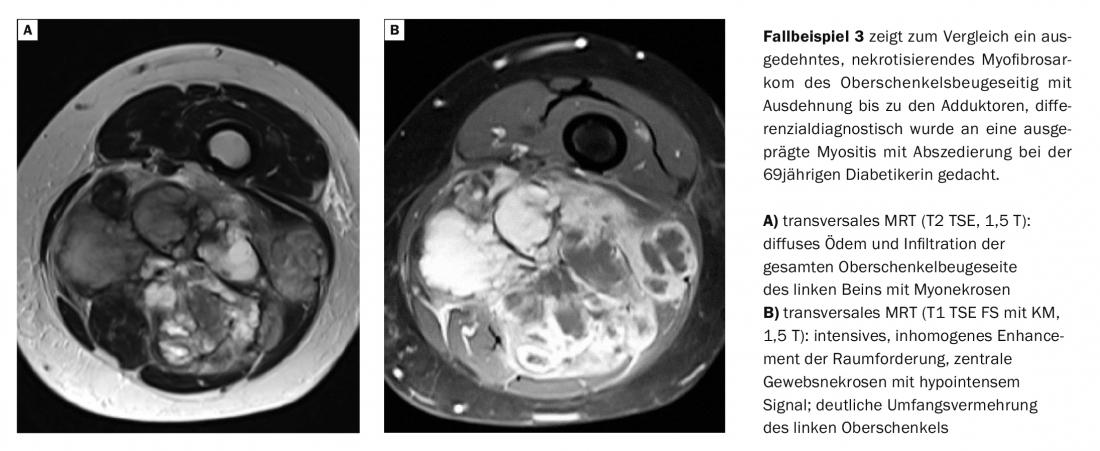

Le miopatie infiammatorie sono sempre più osservate come complicazione dell’infezione da HIV, fino al 72% dei casi [2]. Dal punto di vista dell’immagine, la miosite ascessuale può essere difficile da distinguere dal miosarcoma con necrosi tumorale [3].

La miosite focale si differenzia per il modello di coinvolgimento (singolo muscolo o compartimento muscolare interessato) e mostra un chiaro aumento del contrasto senza ascesso o necrosi del tessuto. Sono colpiti soprattutto i singoli muscoli della parte inferiore della gamba. Le calcificazioni sono comuni nella miosite parassitaria e le intense reazioni di contrasto accompagnate da necrosi tissutale e ascessi sono quasi regolari nella miosite indotta da agenti patogeni. Le reazioni del tessuto edematoso richiedono l’uso di sequenze a soppressione di grasso per una rilevazione affidabile [9]. Tuttavia, l’evidenza di edema non è solo un’espressione di infiammazione, come mostra la Tabella 1 in termini di diagnosi differenziale.